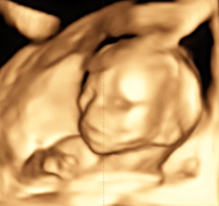

4D-Ultraschall

Der 4D-Ultraschall ist eine Methode der Ultraschall-Untersuchung, bei der das Ultraschallgerät ein dreidimensionales Bild des Untersuchungsobjekts in Echtzeit erzeugt.

Hier zeigt ein kleiner Film einen 4D-Ultraschall

Klicken, um den Film zu sehen